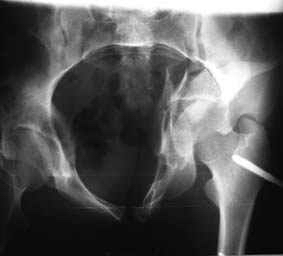

Все-таки надо бы начать не с КТ, а с обзорного снимка таза и косых проекций впадины.

Это обзорные и косые снимки

С уважением,

Leonid

Привет, Леонид. Оскольчатый высокий двухколонный перелом в такие сроки трогать не надо, т.к. это про такие переломы сказано: "кто с ножом на Ж. пойдет тот в ней и останется...".